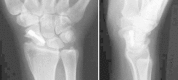

Figure 2

Anteroposterior and lateral radiographs showing pseudarthrosis of the scaphoid in the middle third.